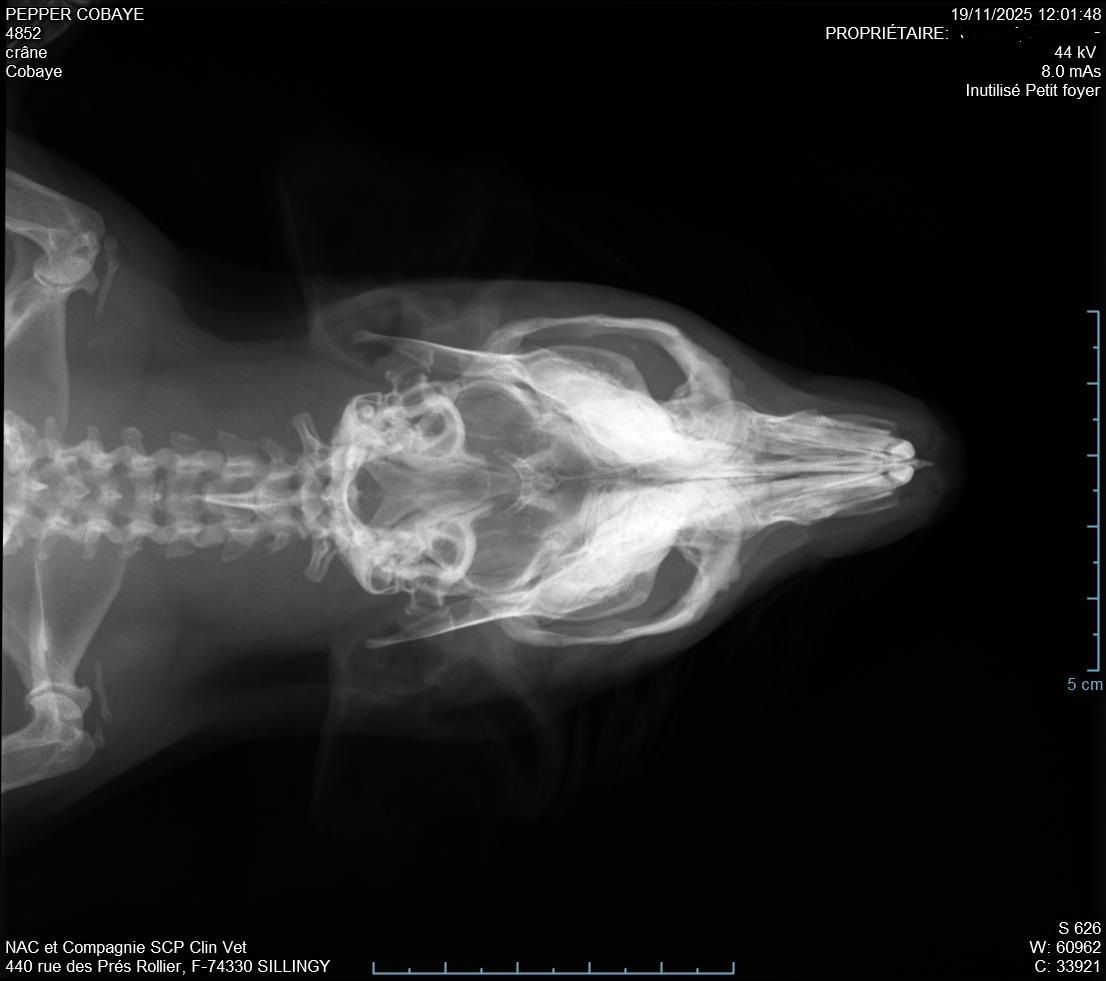

Descendu à 987g donc pas trop bougé depuis la semaine d'avant. La plaie était atone et moins belle que la semaine d'avant (pronostic pas très bon), il a fait des radios pour voir s'il n'y avait pas un problème avec ses dents mais il n'a rien vu, si pas d'amélioration il n'a pas d'autre solution. Nous somme donc repartis pour 10 jours avec un 2eme antibio en continuant le Corylap, Flagyl 125mg/ml 1ml 2x/jour + Contramal 2 à 4 gouttes 2x/jour et toujours Métacam avec le même dosage + Elugel 2x/jour sur la plaie. Changement de gavage pour Critical Care herbivore.